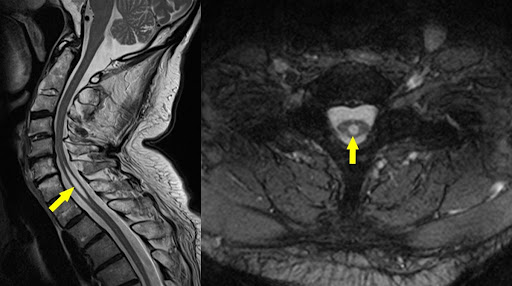

owl eye sign

spinal cord infarct

anterior horn cells